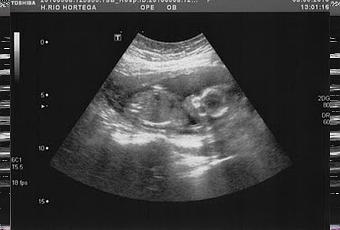

A mediados de febrero, pude retomar la medicación.El 1 de marzo fue el día que me hicieron la amnio. Qué duro fue, me pasé la prueba llorando, aterrada. El día 10 supimos que el feto no tenía la enfermedad genética que temíamos. El 19, se decartó el síndrome de down y otras anomalías cromosómicas, se nos comunicó que era una niña sana- Ese fue el día en que hicimos público el embarazo, así presentamos a nuestra muñeca: